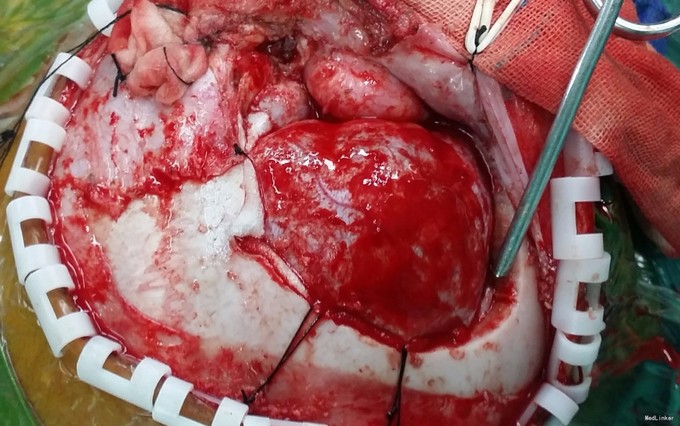

完善相关检查,在气管插管麻下行“左额眶部占位病变切除术”。术后病理诊断为“(左眼眶)丛状神经纤维瘤”。术后给予患儿脱水、营养脑神经、抗感染等对症治疗。复查CT未见明显异常。